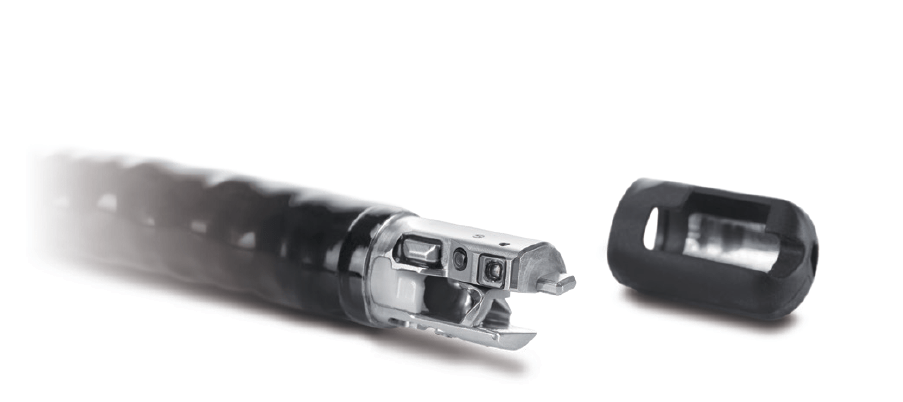

Didelis 4,2 mm kanalas leidžia praleisti daugumą priedų ir prietaisų. Dvigubas fiksavimo mechanizmas, įmontuotas į žnyplių keltuvą, sumažina prieigos praradimo riziką ir palengvina patogų priedų keitimą.

Nuimamas distalinis dangtelis suteikia prieigą prie žnyplių elevatoriaus, taip užtikrinant griežtą ir kruopštų valymą.